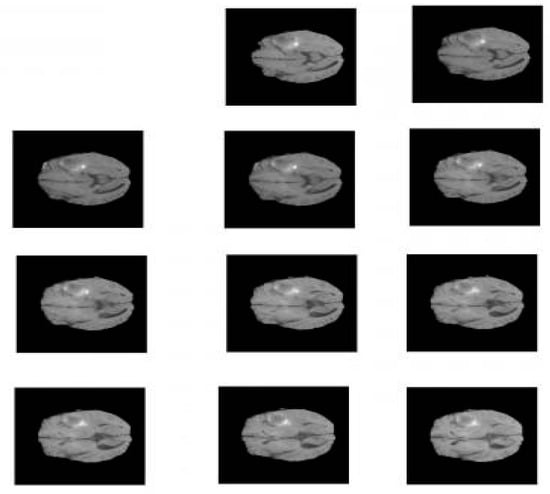

BraTS 19 has been utilized for brain MRI images with a focus on the segmentations of brain tumors on multi-model magnetic resonance imaging (MRI) scans. BraTS contains MRI.jpg format images of 240 × 240. It contains 3762 brain MRI images of both males and females (see Figure 3) [3].

Figure 3.

Sample images from BraTS.